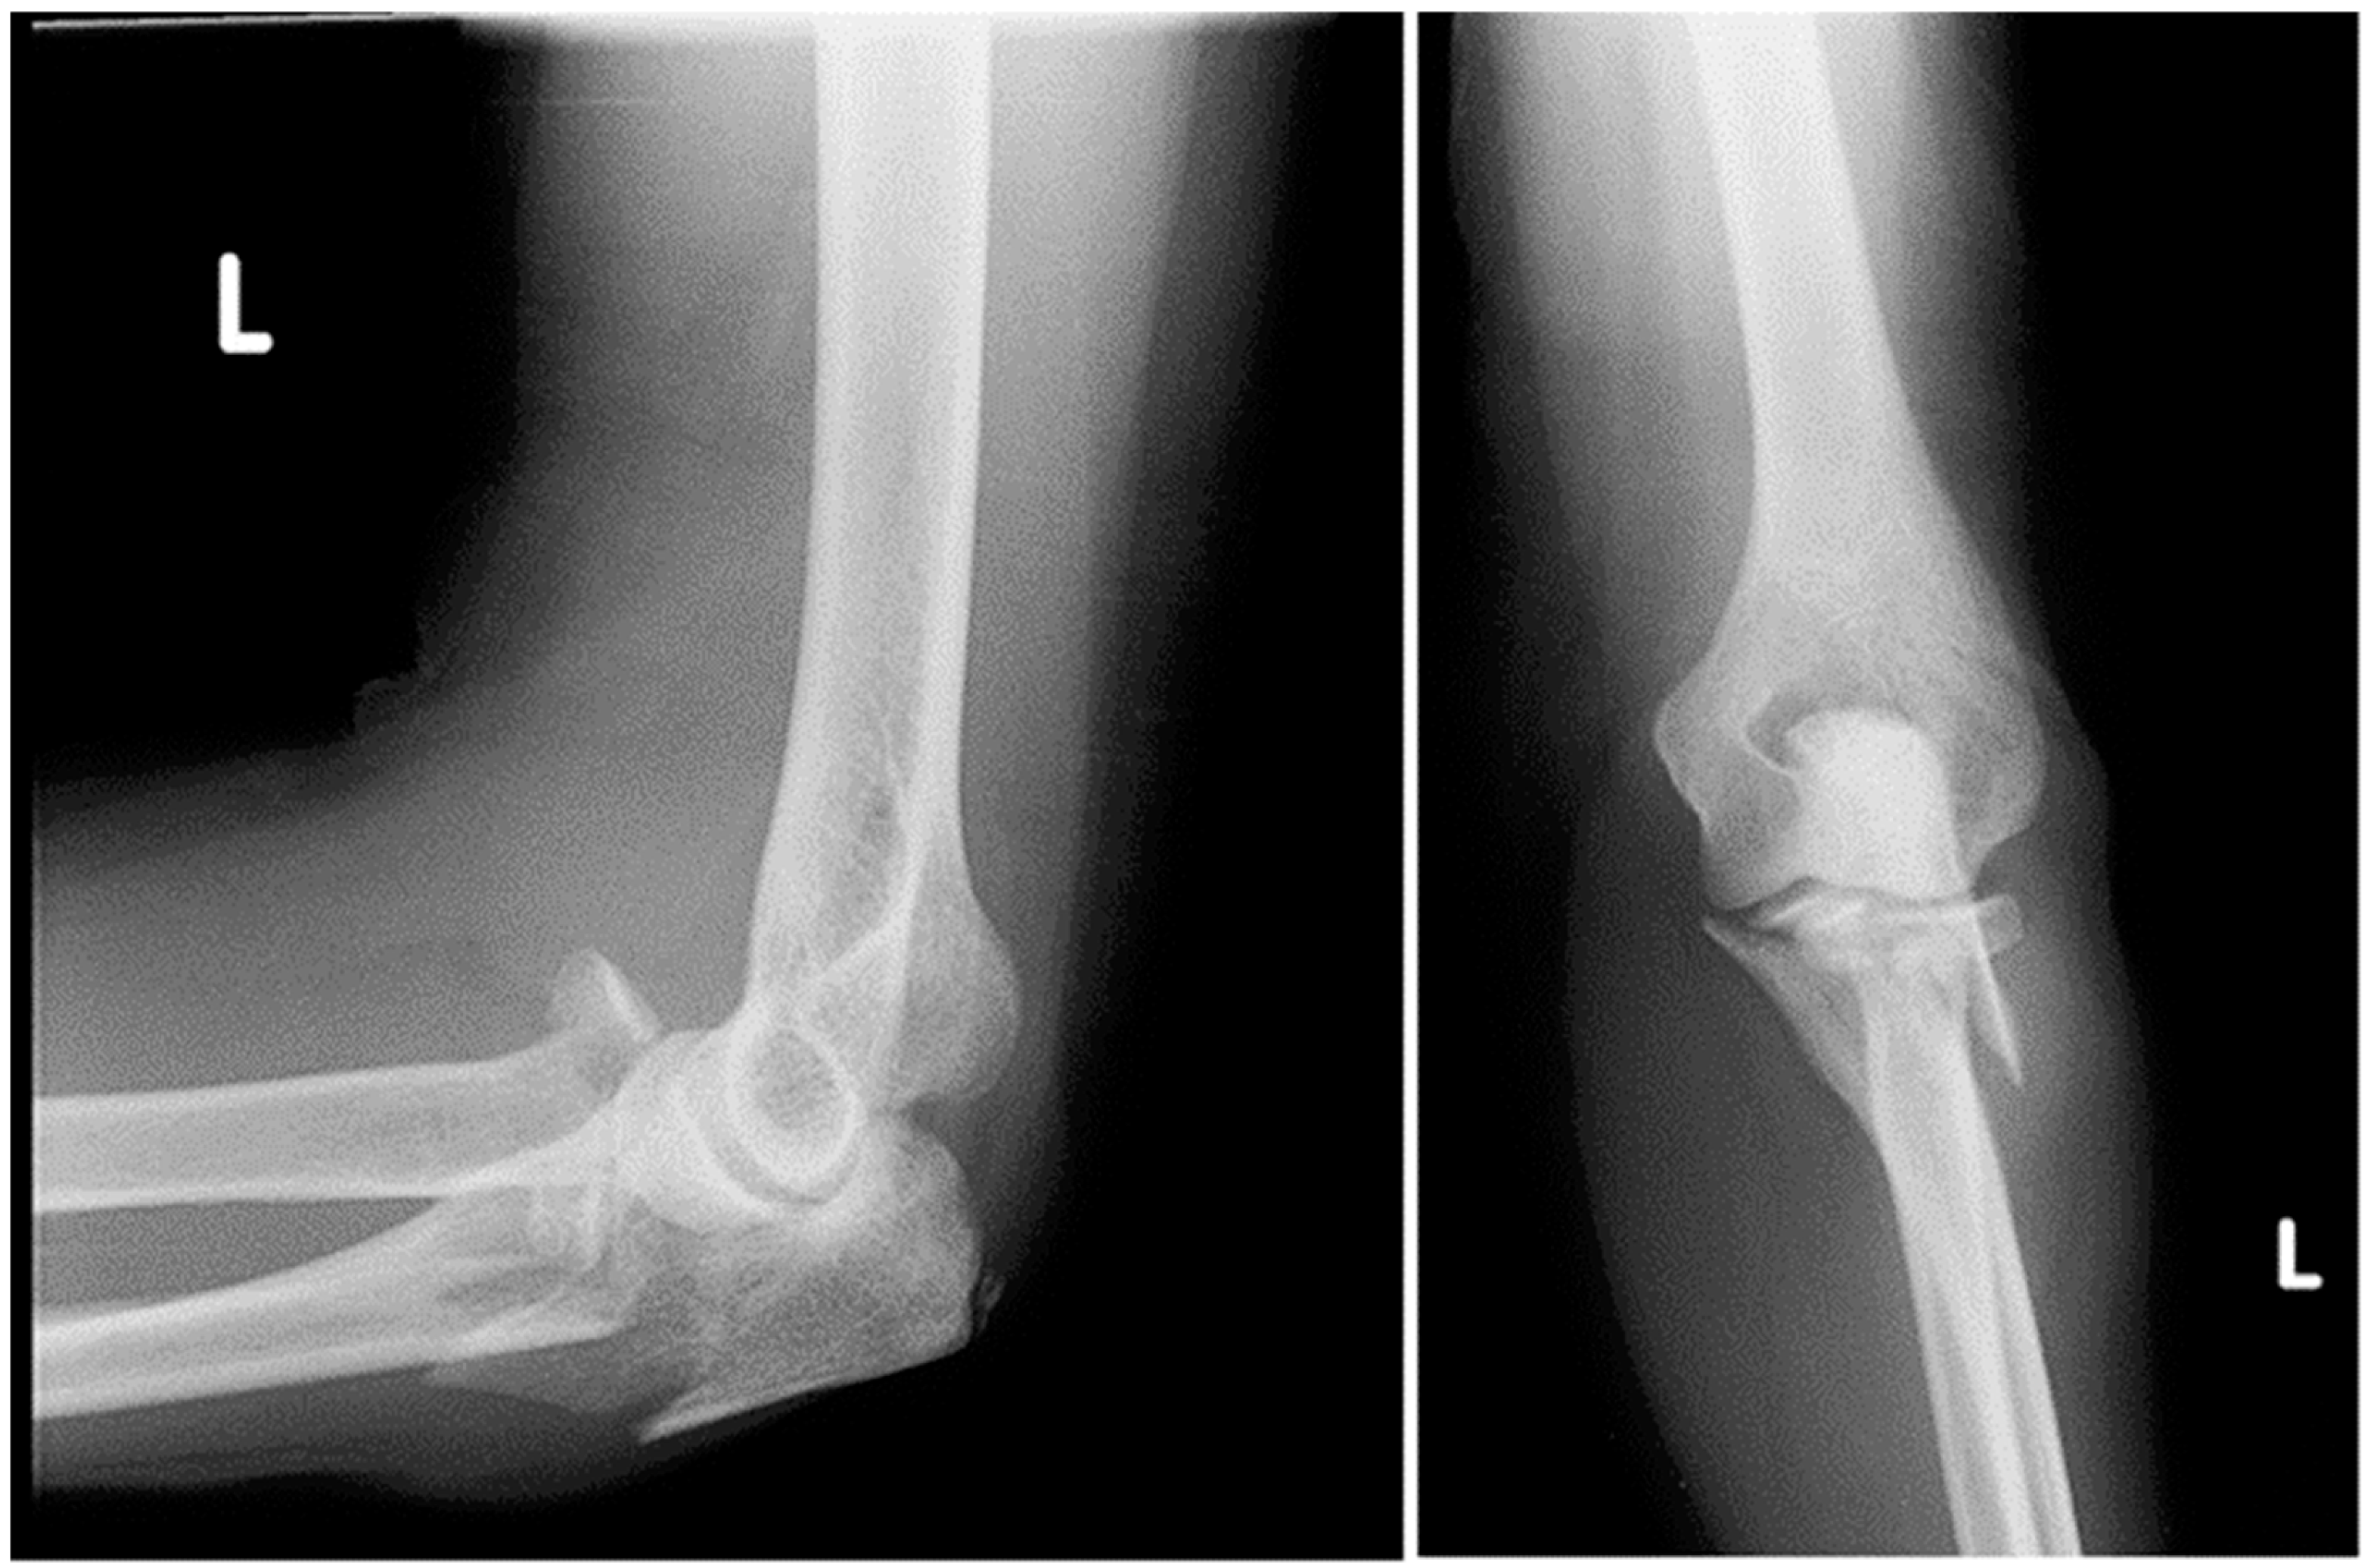

The radiographic presentation of this injury is illustrated in Figure 1.

Figure 1.

Preoperative lateral and anterior-posterior X-ray radiographs of the left elbow demonstrating a Monteggia-equivalent fracture.